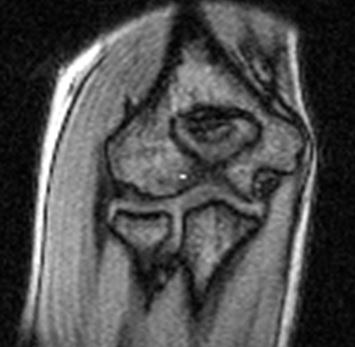

(屋外で撮影された、小5女子の肘の画像です。内側側副靭帯などのこまかな構造もよくみえます。非常に高い画質です)